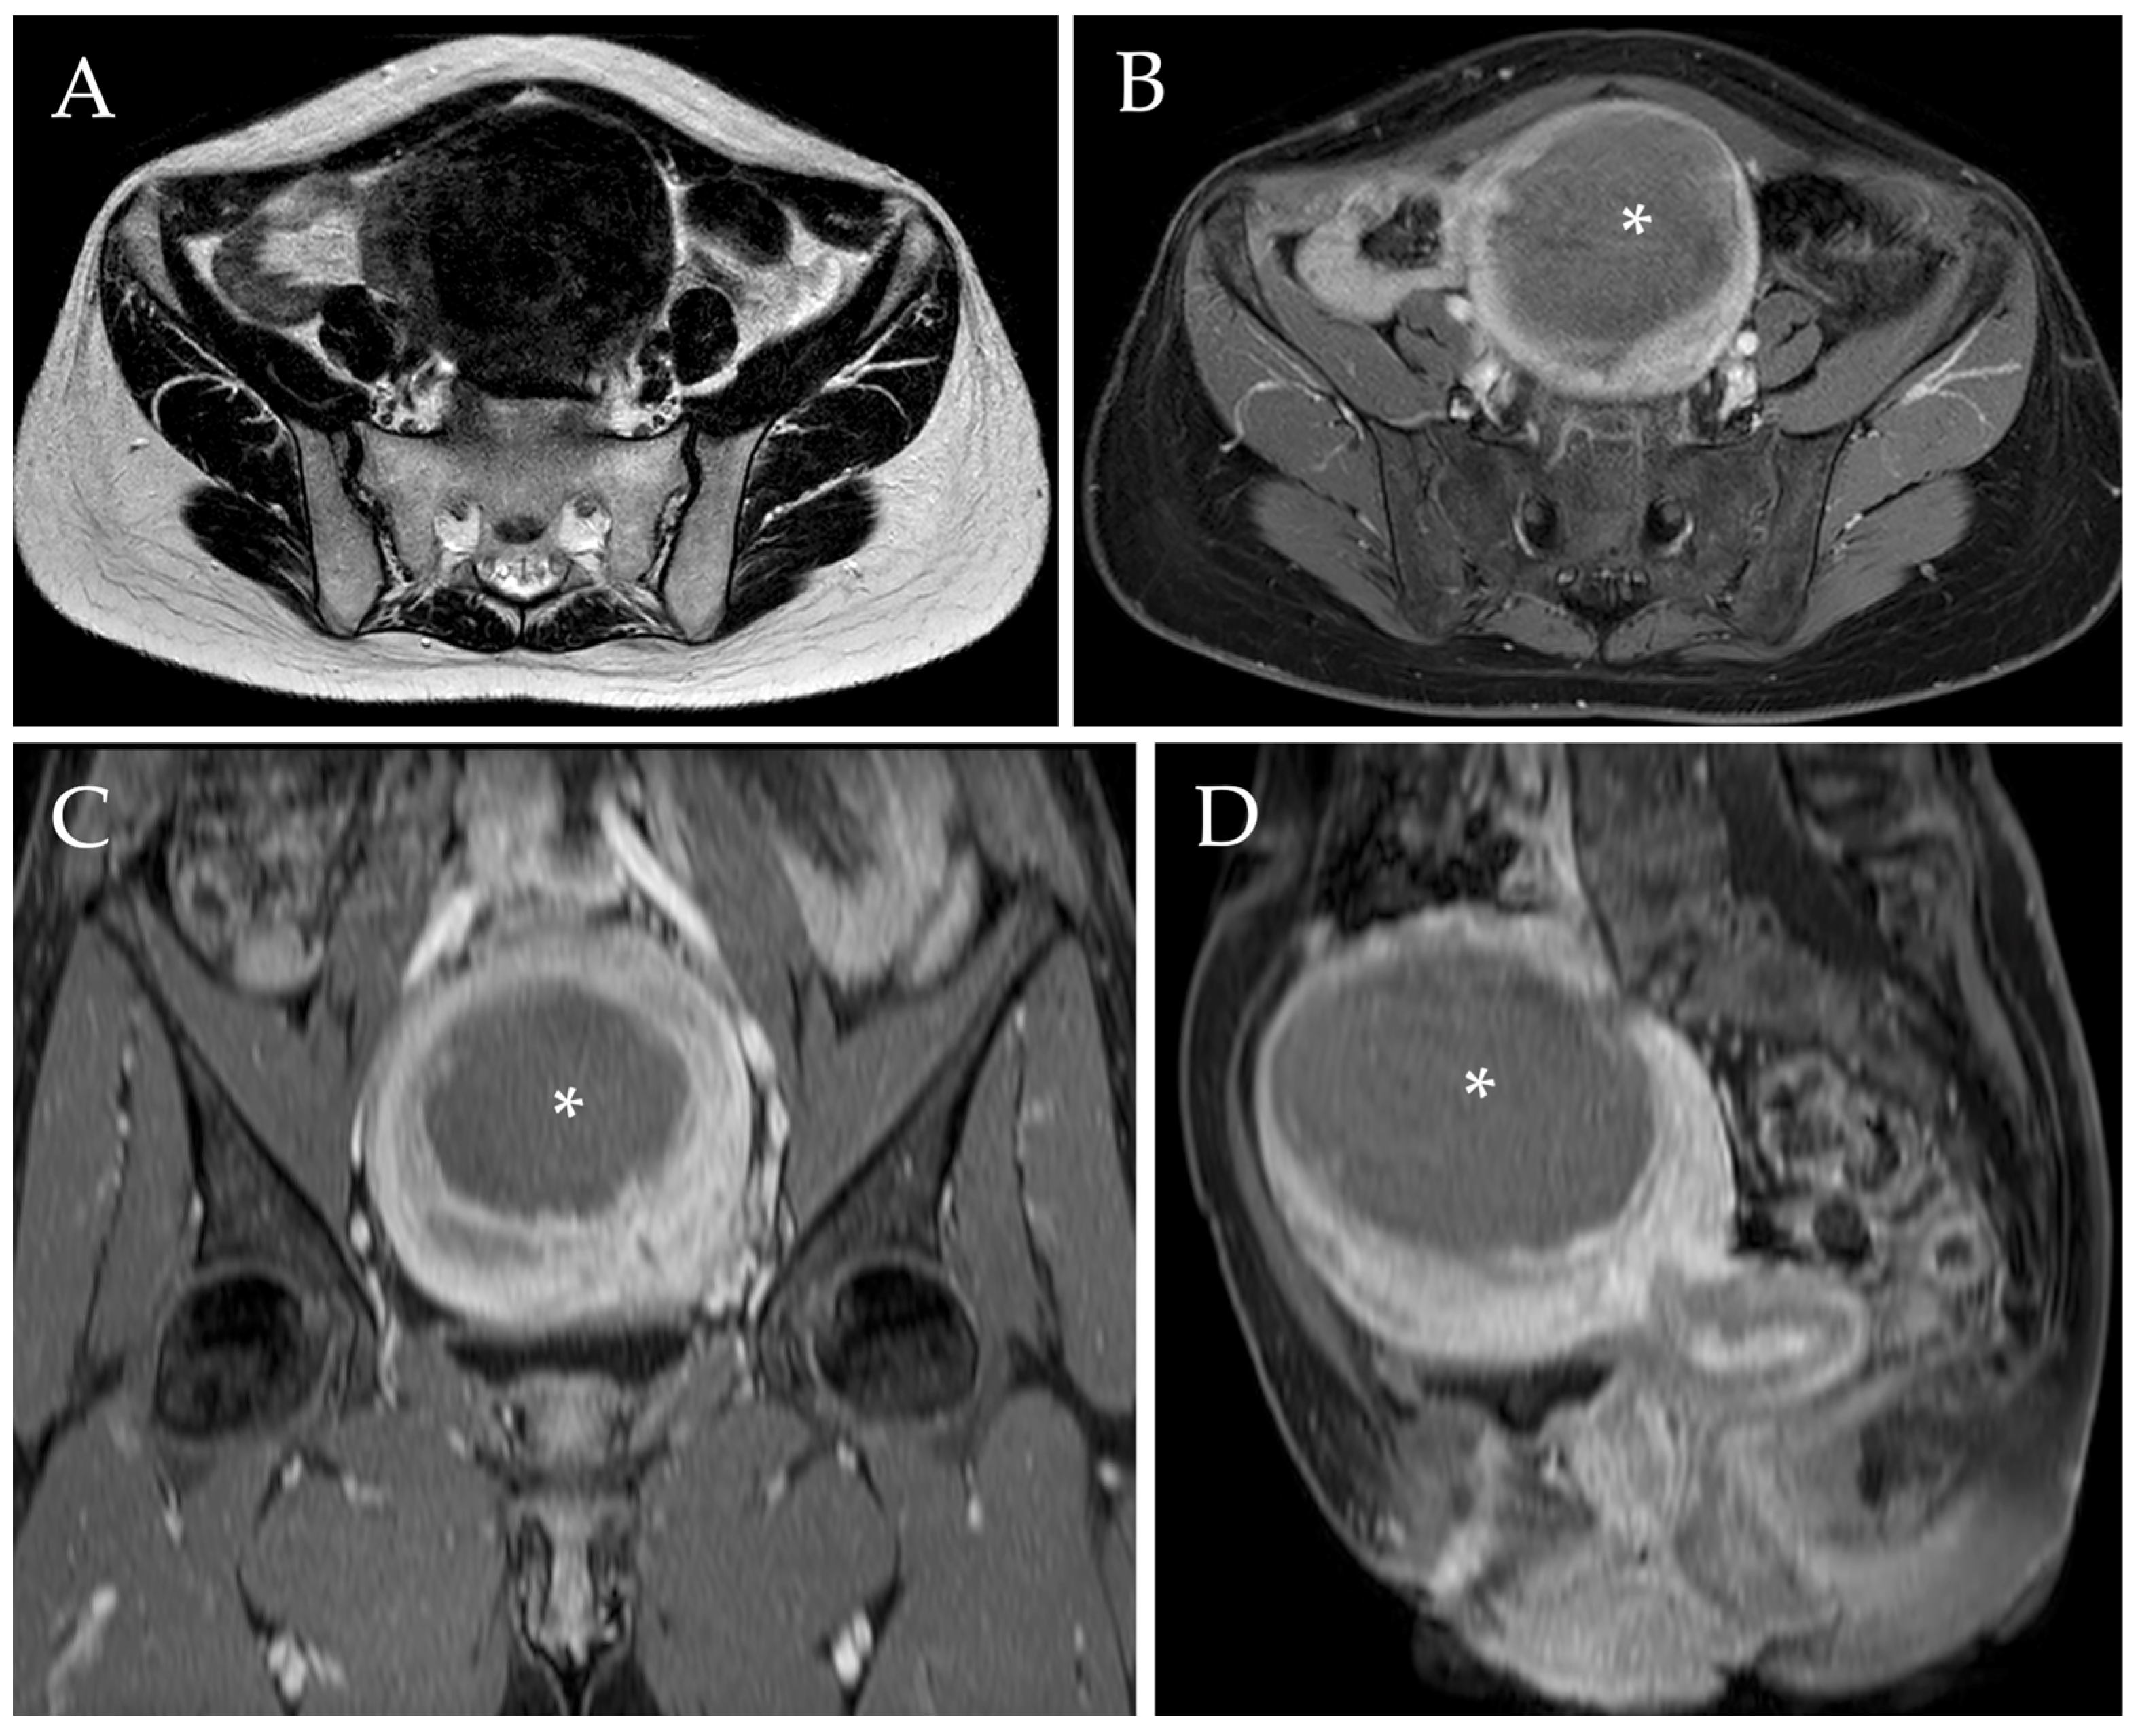

The mean uterine fibroid diameter was 74 (±30.1) mm before UAE, which was reduced to 42.2 (±30.1) at the 1-year follow-up after embolization ((mean reduction of 31.8 mm (±20.4)). This is equivalent to 42.6% (±21.6%) overall uterine fibroid diameter response (Figure 4). More specifically, solitary myomas presented a 40.4% (±20.6%) decrease in their diameter, whereas the dominant myoma in patients with multiple masses showed a diameter reduction of 43.8% (±16.4%) (p = 0.470) (Table 3).

Figure 4.

Post-procedural MRI of the same patient. Axial T2-w image (A) demonstrated a reduction of the diameter of the voluminous myoma after UAE, which now measures approximately 90 mm (i.e., a diameter reduction of 35.7%). Axial, sagittal, and coronal post-contrast T1-w images with fat saturation (B–D) confirmed the diameter reduction and revealed the presence of a wide intra-tumoral necrotic area (white asterix).